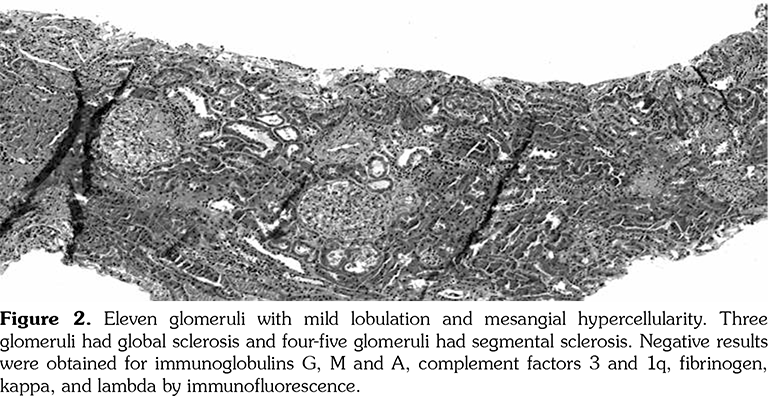

A 14-year-old female patient referred to our clinic with headache and dizziness for two weeks and loss of consciousness for about 10 minutes. On admission, the blood pressure was 90/60 mmHg and all peripheral pulses were palpable. Her body weight was above 97th percentile for her age and body mass index was 33. The fundus examination and other organ systems were essentially normal. Laboratory studies revealed erythrocyte sedimentation rate (ESR) as 108 mm/hour and C-reactive protein (CRP) as 7.5 mg/dL (0-0.8), while other measurements were normal. Urinalysis revealed microscopic hematuria and proteinuria of 31.9 mg/m2/hour in 24-hour urine collection. The cerebrospinal fluid examination showed no abnormalities. Cranial magnetic resonance imaging (MRI) showed multiple millimetric hyperintense deep white matter lesions on T2-weighted imaging (Figure 1). Intracranial and extracranial arteries were normal in magnetic resonance angiography (MRA). Renal biopsy findings were interpreted as FSGS (Figure 2). Patient was considered as cerebral vasculitis and incidental FSGS. Pulse methylprednisolone therapy for three consecutive days was initiated and continued with oral prednisolone. At four years of follow-up, proteinuria decreased to 5-15 mg/m2/hour, and ESR and CRP were normal. Repeated brain MRI and MRA examinations showed no new lesions. Four years later, at the age of 18, on a routine examination, both radial artery pulses were absent and the blood pressure could not be measured. Significant bruit was heard on the left carotid artery. Laboratory studies revealed ESR as 43 mm/hour and CRP as 2.46 mg/dL. Aortic MRA revealed diffuse wall thickening and contrast enhancement in the arcus aorta and its many main branches (Figure 3). Takayasu arteritis diagnosis was established according to the European League Against Rheumatism/ Paediatric Rheumatology International Trials Organisation/Paediatric Rheumatology European Society criteria.[2] Methotrexate was begun, and daily prednisolone was continued. Four months after the diagnosis of TA, left-sided hemiparesis developed. Brain MRI demonstrated a wide cerebral infarct at the right anterior vascular territory (Figure 4). Brain and neck computed tomography angiography showed total occlusion of the right internal carotid artery. Vascular involvement of the right common carotid artery was progressed to preocclusive stenosis. Diameters of the right anterior and middle cerebral arteries were thin and fed by the posterior and anterior communicating arteries (Figure 5). Tocilizumab treatment was started at 8 mg/kg every four weeks. At follow- up with 2.5 years of tocilizumab treatment, the patient's clinical condition improved slightly, and no new symptoms developed. A written informed consent was obtained from the patient.

Several causes of ischemic stroke in patients with TA have been described, including embolism from stenotic or occlusive lesions in the aortic arch and its main branches or cardiac diseases.[6] In addition, intracranial stenosis have been observed as a consequence of vasculitic involvement or a prior embolization into the vessel. In our patient, based on the MRI scan, this cerebral accident seemed to be a vascular occlusion.